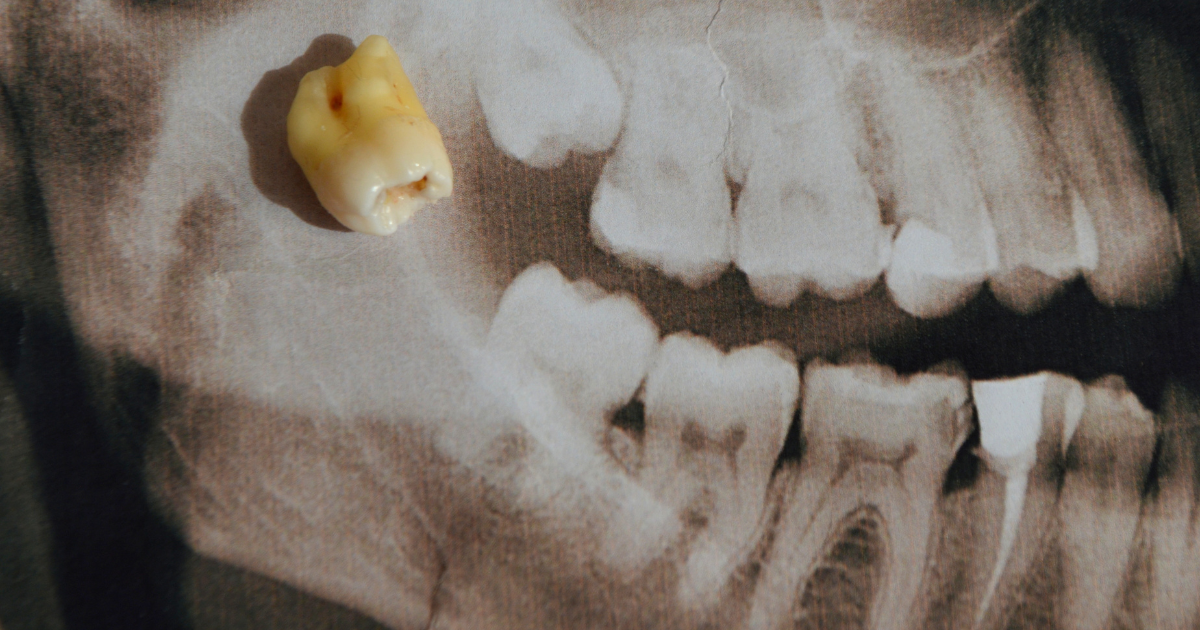

There is no single cause of this condition. It is associated with several different hereditary conditions such as cleidocranial dysplasia, Fabry disease, cleft palate, Gardner’s syndrome, and more.

Shutterstock

For most people, it is not necessary to look into why they have extra teeth, especially if it is only one or two extra. Since they can live their lives normally, there is no reason to do costly and time-consuming genetic testing or look for other triggers.

Whatever the cause, it is an interesting condition, and in more severe cases, it can be very impactful. If you have hyperdontia, the best thing to do is to speak with your dentist to determine what, if any, treatment is necessary.